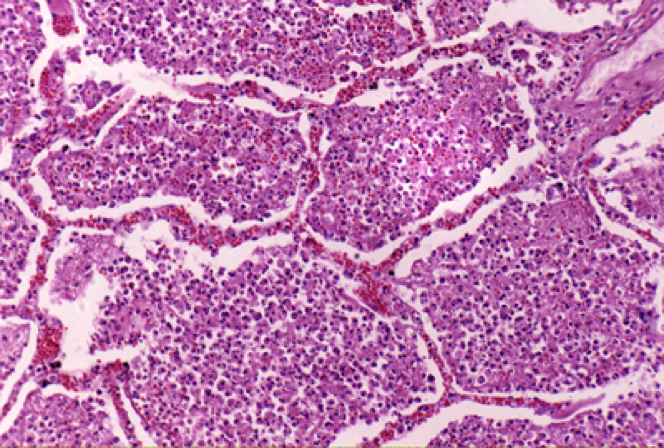

(一)变质—— 损伤

炎症局部组织所发生的变性和坏死称为变质(alteration)。变质既可发生在实质细胞,也可见于间质细胞。例如:病毒性肝炎: